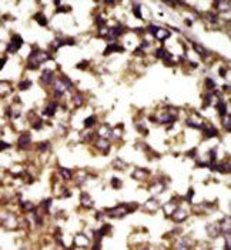

Supportive validation

- Submitted by

- Acris Antibodies GmbH (provider)

- Main image

- Experimental details

- Formalin-fixed and paraffin-embedded human cancer tissue reacted with the primary antibody, which was peroxidase-conjugated to the secondary antibody, followed by DAB staining.